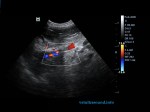

- Infiltration of the caudal vena cava by the adrenal gland, which had infiltrated all the surrounding tissues.

- Thromboses were present on the right and left renal vein due to stenosis of the caudal vena cava.

Infiltration of the caudal vena cava caused by the left adrenal gland mass, thromboses of the right and left renal veins, lesions potentially metastatic in the liver and clinical manifestation of pancreatitis probably induced by high levels of corticosteroids.